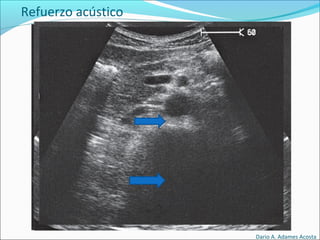

Refuerzo acústico : Imagen hiperecogénica después de

que el haz atraviesa un elemento quístico.

Refuerzo acústico

Dario A. Adames Acosta